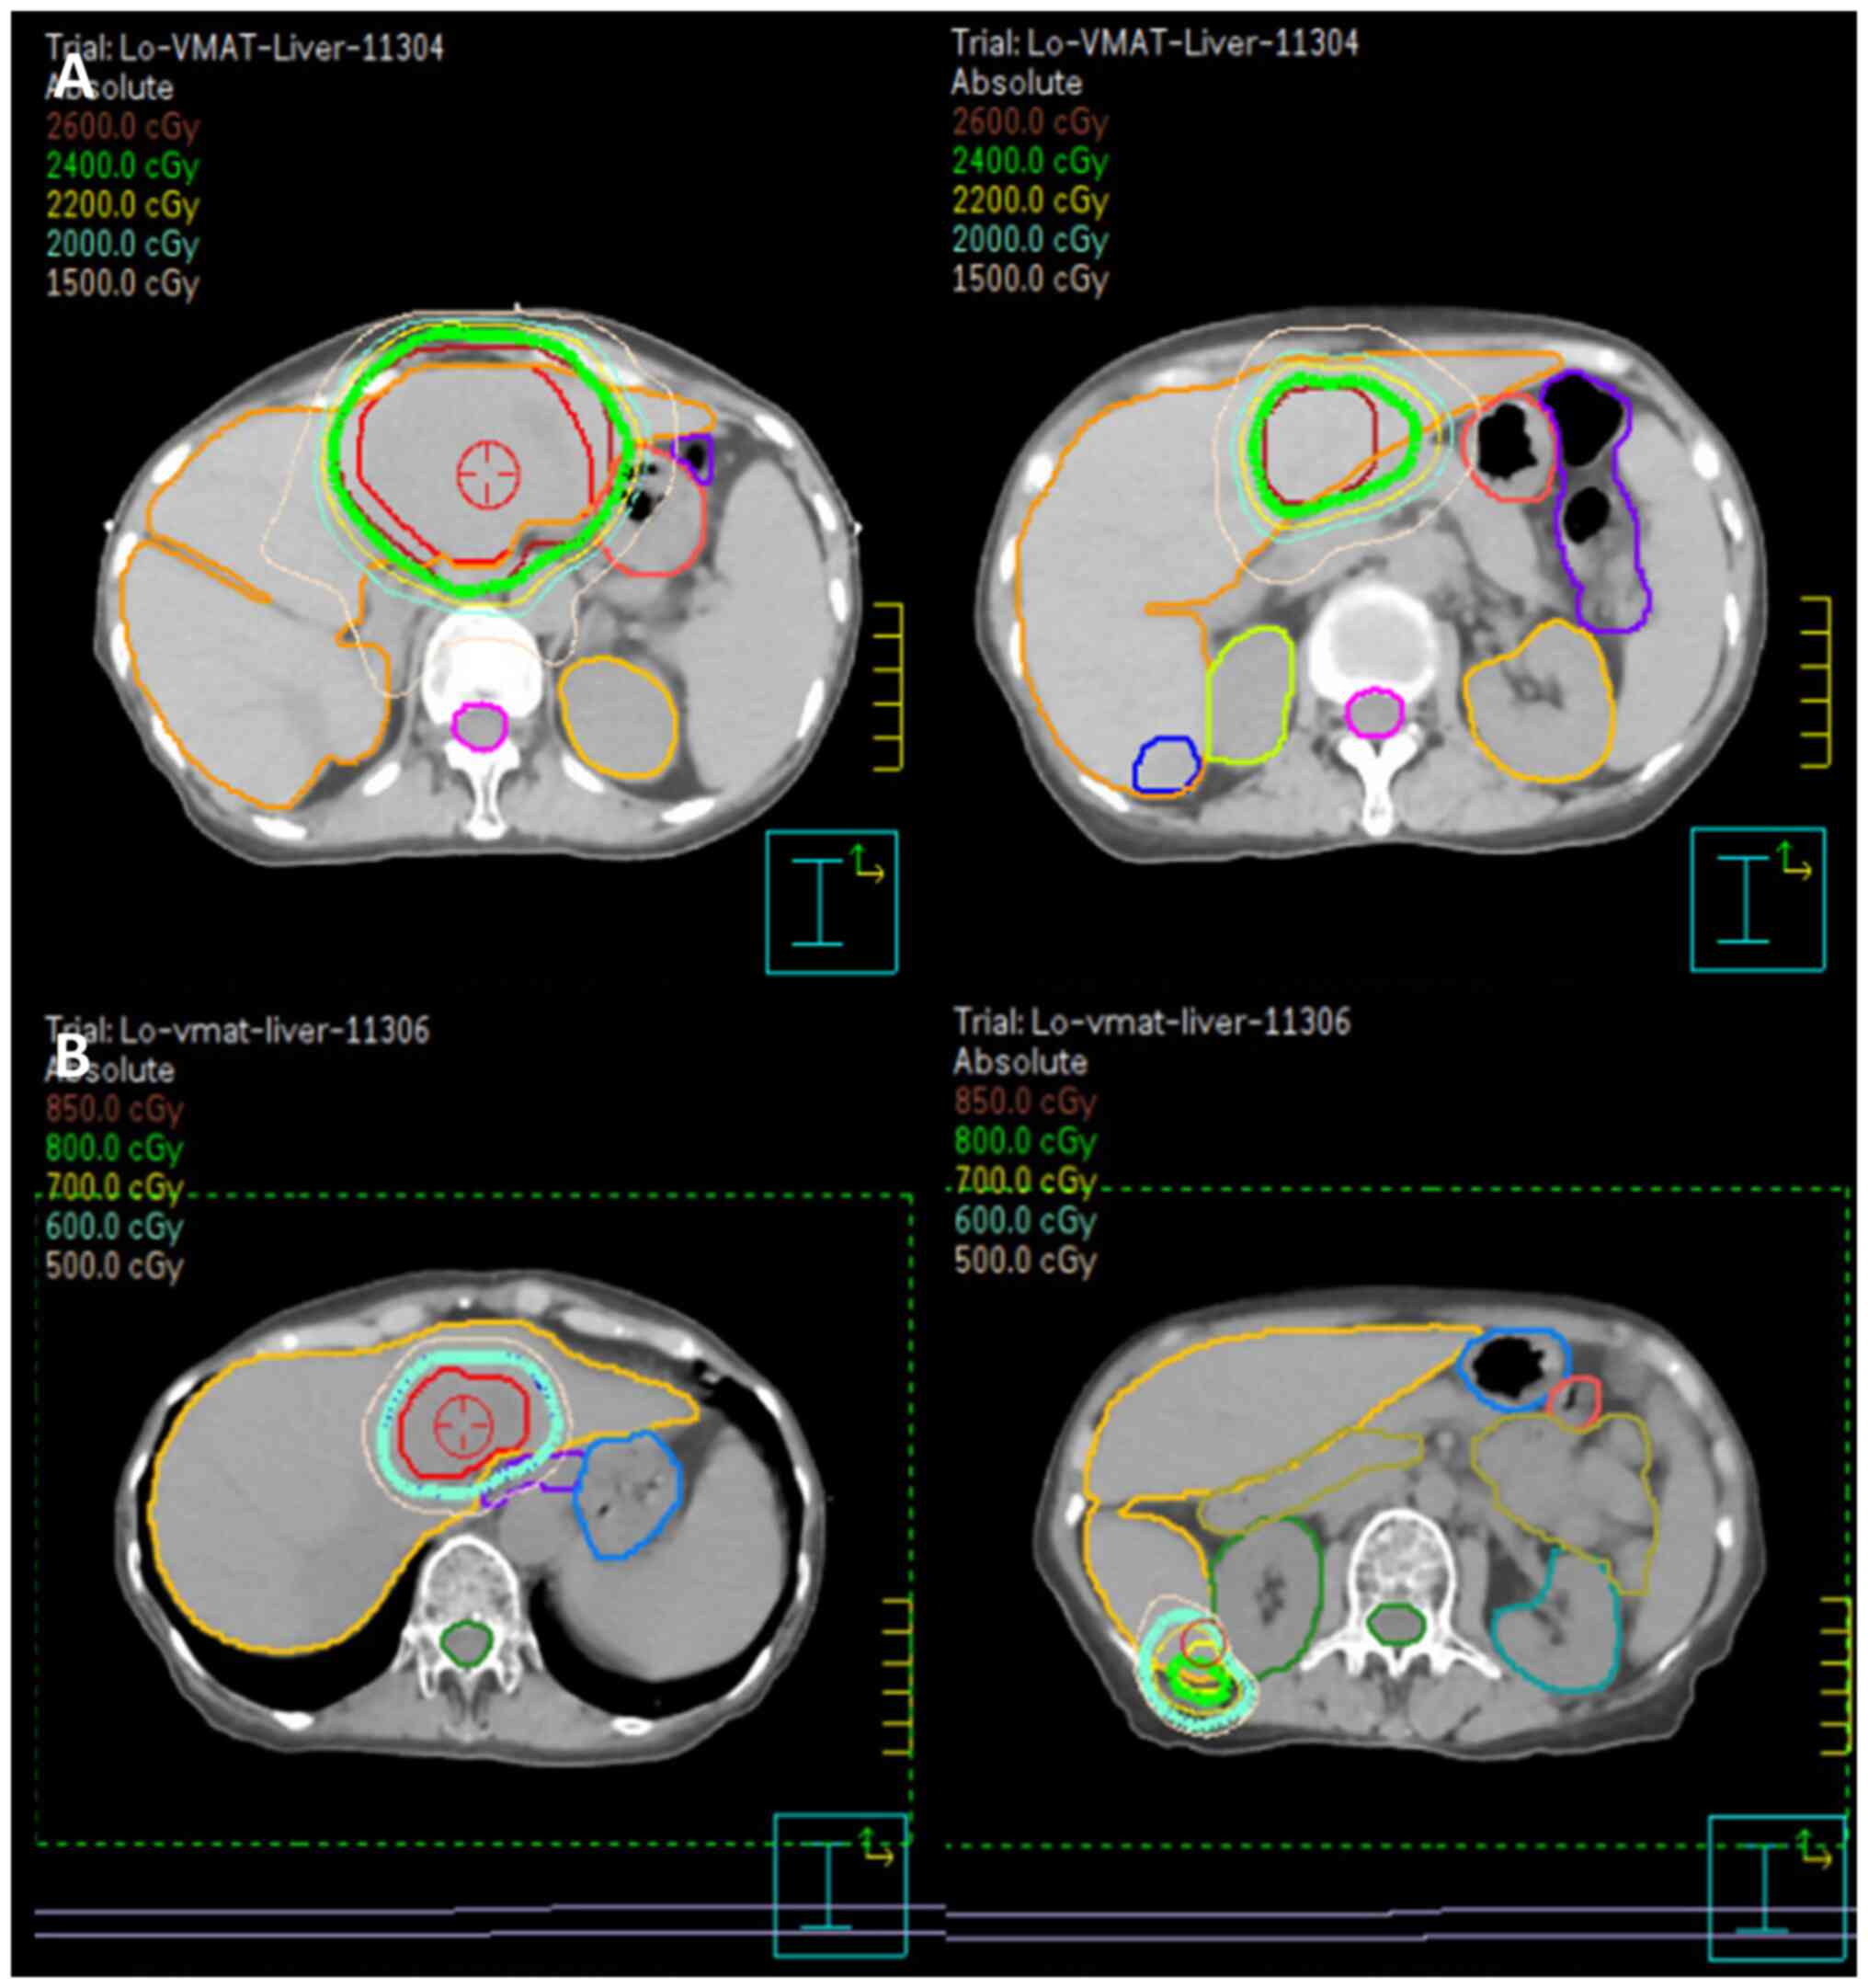

Owing to immunodeficiency and the risk of pancytopenia, chemotherapy was not suggested by the hematologist. Considering the size and location of the hepatic lesions, as well as the patient's overall health and comorbidities, a multidisciplinary team decided to proceed with involved site radiotherapy (ISRT) as the primary modality. Given the bilateral lobe involvement, huge tumor burden and relatively small normal liver volume, a stepped response-adapted approach was planned. A radiation therapy plan of 24 Gy in 16 fractions for the larger tumor was first developed and administered in March 2024 (Fig. 5). Four-dimensional CT (4DCT) was employed during the treatment planning phase to account for respiratory motion. By capturing tumor movement across various respiratory phases, 4DCT enabled the creation of a motion-compensated treatment plan, ensuring precise targeting of hepatic lesions while minimizing the radiation dose to surrounding normal tissues. The larger tumor was irradiated first, with the smaller tumors primarily receiving a scatter dose (mean dose, 447.4 cGy). During the radiotherapy course, significant tumor shrinkage was observed, with the tumor diameter decreasing from 154.9 to 131.4 cm3 and the volume from 6.6 to 5.1 cm3. This prompted the first adaptation of the radiation plan, which involved re-defining the clinical target volume to reflect the reduced tumor size. The updated plan was applied for the last four fractions of radiotherapy, starting from the 13th fraction. The patient tolerated radiotherapy well, with only grade I gastrointestinal upset, graded according to the Common Terminology Criteria for Adverse Events (CTCAE), version 4.0 (8). The patient showed no signs of immunosuppression or the deterioration of pre-existing conditions. Throughout the radiation therapy period, laboratory assessments, including hematological, liver and kidney function tests, demonstrated results within normal limits. Follow-up MRI at 1 month after the first radiotherapy plan showed a marked reduction in both directly irradiated and non-irradiated lesions. For the initial ISRT plan (Fig. 5A), the tumor volumes were 154.9 and 6.6 cm3 for the larger and smaller tumors, respectively. The normal liver volume was 798 cm3. For the response-adapted plan (Fig. 5B), after significant tumor shrinkage, the tumor volumes reduced 38.98 and 2.78 cm3, respectively. The normal liver volume increased to 913.13 cm3. These changes were observed during follow-up imaging, which prompted the response-adapted plan prescribing boost doses of 6 and 8 Gy to the residual lesions in segments 2/4a and 6, respectively (Fig. 5). Consequently, a local radiation boost to the bilateral hepatic lesions was planned, delivering an additional 6 Gy to the segment 2/4a tumor and 8 Gy to the segment 6 tumor in four fractions. At 4 months post-treatment, follow-up MRI (Fig. 6) demonstrated no evidence of residual malignancy. At 7 months post-treatment, whole-body PET revealed no metabolic evidence of malignancy (Deauville criteria score 1) (9) (Fig. 6). No abnormal indicators were observed in the physical, hematological or hepatological examinations at the follow-up evaluations, which were performed every 3 months. This schedule will continue for at least 2 years and may transition to every 6 months based on the patient's condition and physician's assessment. The patient remained healthy and without signs of relapse following radiotherapy.

Figure 6.

Post- involved site radiotherapy images. (A) Magnetic resonance imaging at 4 months and (B) positron emission tomography scan at 7 months demonstrating no evidence of malignancy.

In the present case, response-adapted radiation therapy was used to optimize the dose delivery. Typically, this approach includes assessing the tumor response to an initial radiation course or another treatment modality using imaging or diagnostic tools. Based on this assessment, the radiation plan is adjusted in terms of dose, target area or technique to maximize treatment efficacy while minimizing damage to the surrounding healthy tissues. A similar response-based approach was demonstrated in a phase II trial by Pinnix et al (22), which investigated radiotherapy for orbital indolent B-cell lymphoma, employing a response-adapted ultra-low-dose protocol initiated with a 4-Gy dose, followed by an additional 20 Gy for cases of persistent disease. The trial demonstrated a 2-year local control rate of 89.4%, with 90% of patients achieving a complete response and no grade 3 or higher adverse effects. In the present case, radiation therapy dosages and normal tissue constraints were guided by recommendations provided by the International Lymphoma Radiation Oncology Group (23). Considering the bilateral lobe involvement and limited normal liver volume (798 cm3; compared with the average normal adult liver volume of 1,000-1,400 cm3 in females), the larger tumor was irradiated first, with the smaller tumors primarily receiving a scatter dose (mean dose, 447.4 cGy). Using scatter doses for smaller tumors can be appropriate in certain scenarios, given the highly radiosensitive nature of lymphoma (as low as 4 Gy). Although no significant toxicities were observed during the 7-month follow-up, the potential for late toxicity, such as radiation-induced liver disease (RILD) or central biliary tract toxicity, persists, and this is more common in cases with large liver volume irradiation or central lesions. Toesca et al (24,25) highlighted strategies for predicting and mitigating RILD and central biliary tract toxicity, emphasizing the importance of personalized treatment planning and careful dose management to minimize risks. In the present study, subsequent MRI follow-up indicated a partial response, leading to the administration of additional radiation (6 Gy to the segment 2/4a tumor and 8 Gy to the segment 6 tumor, delivered in four fractions). This approach minimizes radiation exposure to the uninvolved normal liver while ensuring adequate treatment for both tumors. In a previous study, in patients with gastric mucosa-associated lymphoid tissue lymphoma treated with definitive radiotherapy, the median time to achieve complete remission was 3.9 months, with some cases requiring >12 months for confirmation through follow-up biopsies (26). This variability underscores the importance of careful, long-term monitoring to evaluate treatment outcomes and ensure sustained disease control.